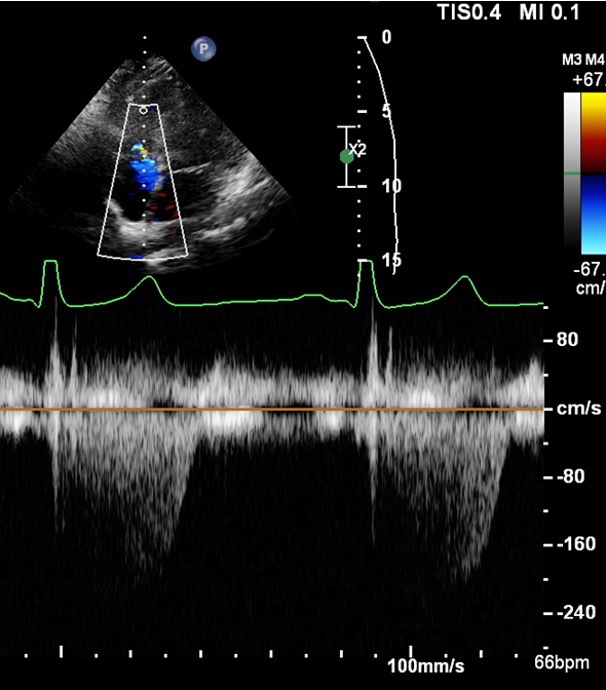

What should we remember when we get a PSAX TV CW clip? 3

A

1. Place the cursor through centre of TR jet, TV coaptation zone if no TR

2. Baseline 1/4 from top with 2.4 m/sec below baseline even if no TR is seen

3. Measure if parabolic jet seen

Should we measure the the TR?

Yes because we can see the peak

10

Q

Should we measure this TR?

No because we would be guessing. See how the furies is right in the blue jet?